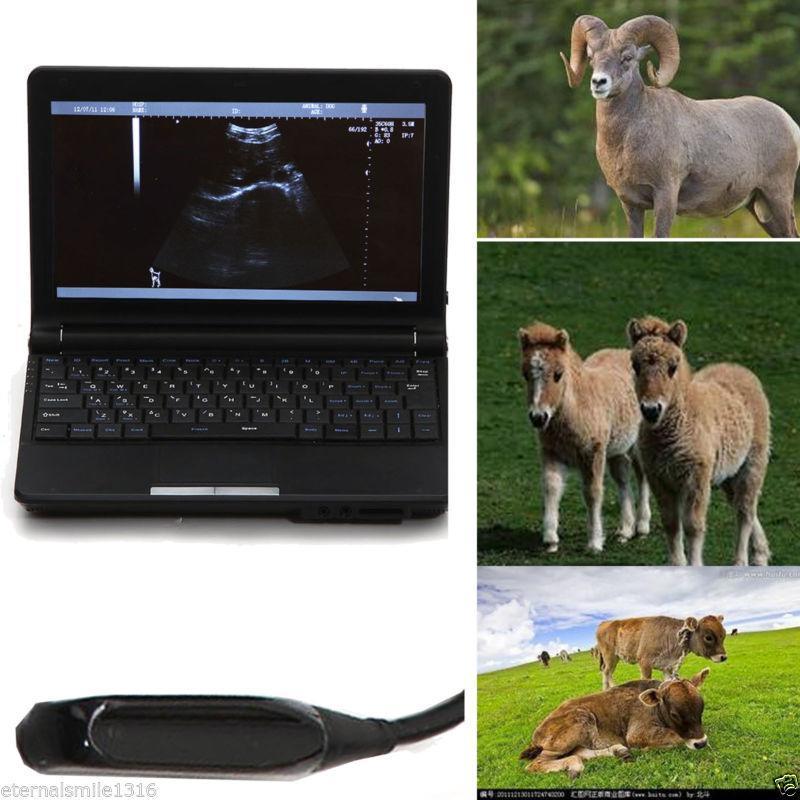

Veterinary vet Digital Laptop Ultrasound Scanner w Rectal Linear Probe 3D A+ 190891459831

Sale price$ 1,955.69

Regular price$ 2,384.99